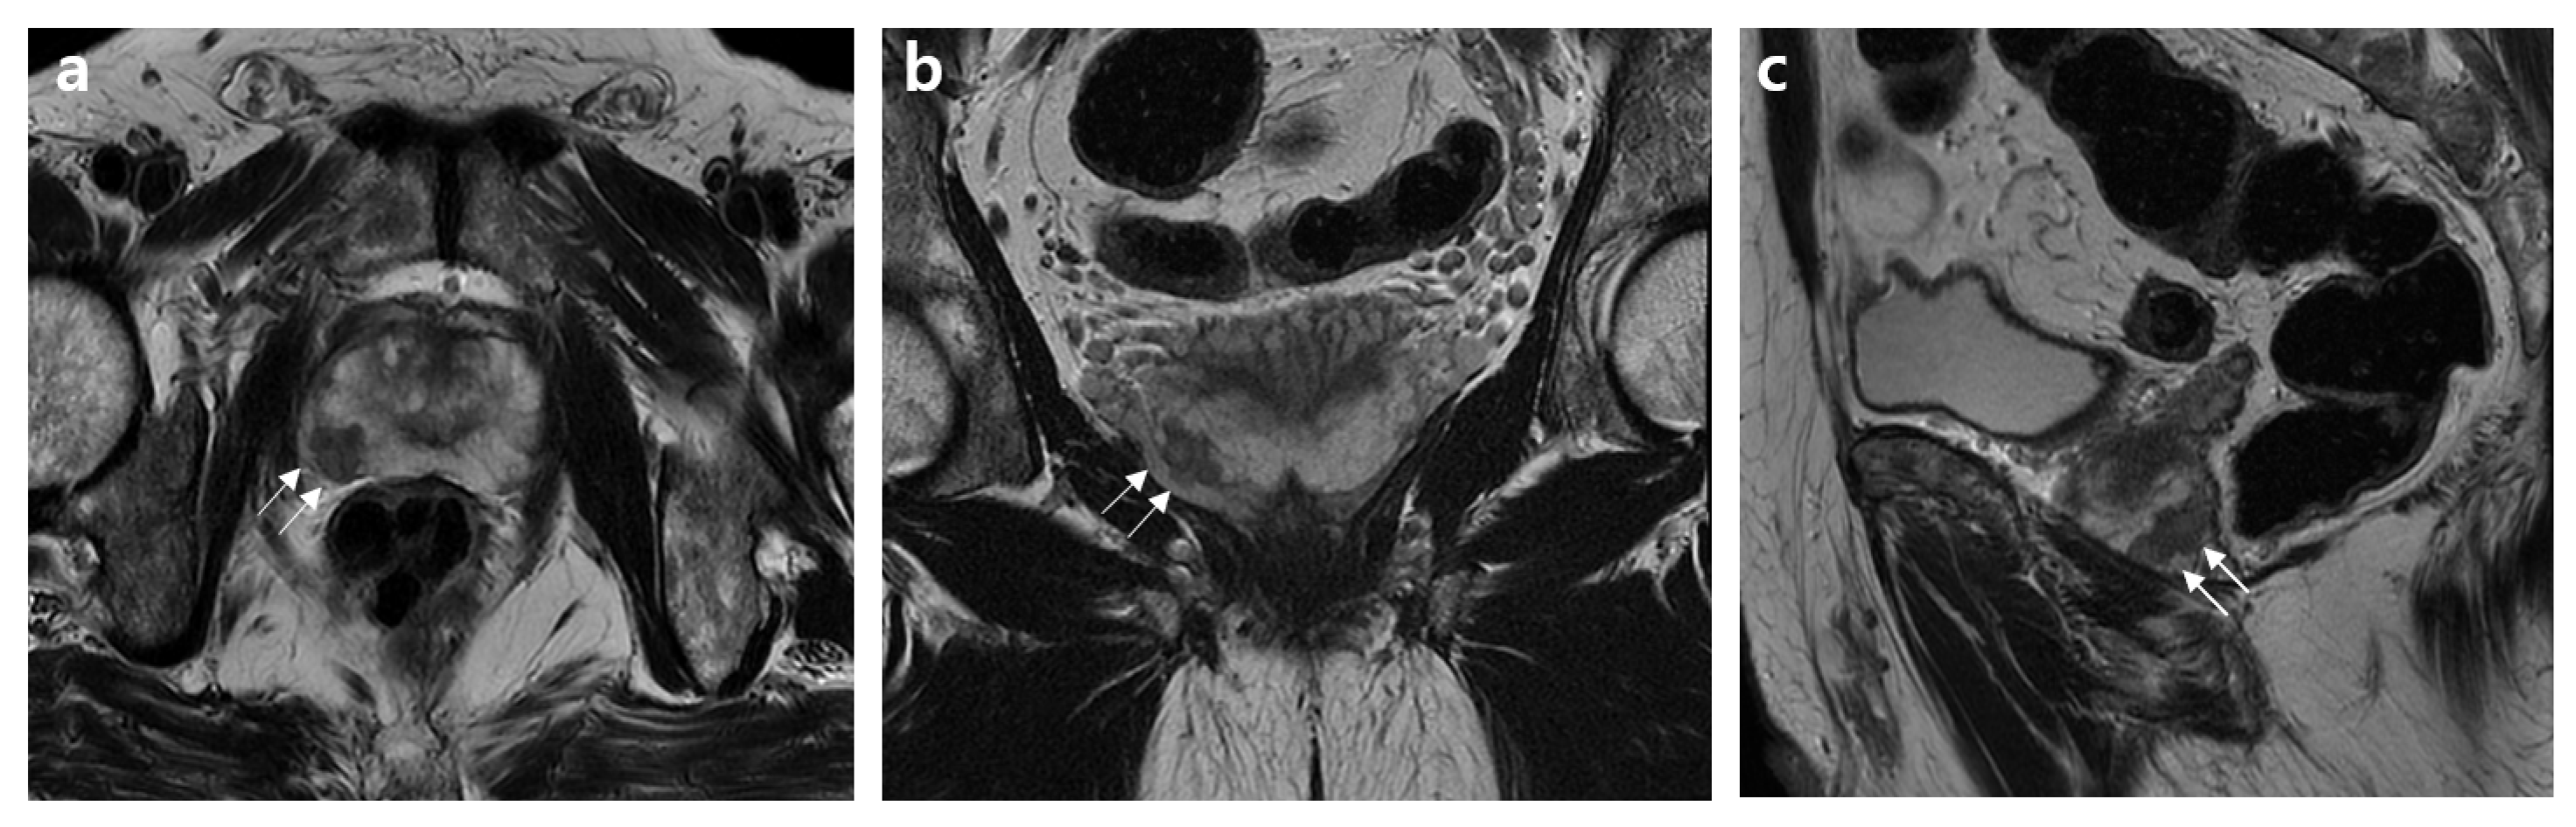

2.2. MRI Assessment